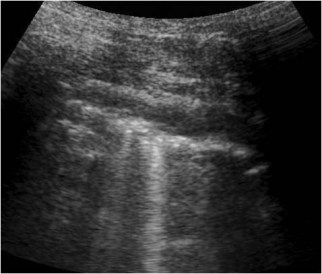

En la ecografía de tórax la pleura se ve como una línea ecogénica que separa el plano muscular del pulmón. En condiciones normales, con la respiración se produce un desplazamiento de ambos planos, movimiento señalado por las flechas blancas. La demostración de este deslizamiento excluye el neumotórax con un valor predictivo negativo y una sensibilidad del 100%. Su ausencia, en cambio, no es diagnóstica de neumotórax ya que puede estar presente en pacientes críticos con atelectasia masiva, intubación de un bronquio principal, contusión pulmonar, enfermedad pulmonar obstructiva crónica, síndrome de distrés respiratorio agudo o adherencias pleurales.